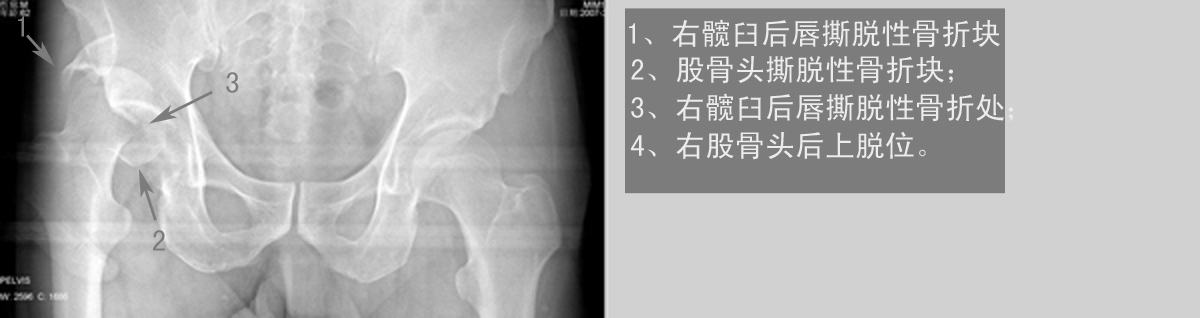

以下是引用dyqct在2007-3-10 15:56:00的发言:[br]骨折。[br][br][br][br]